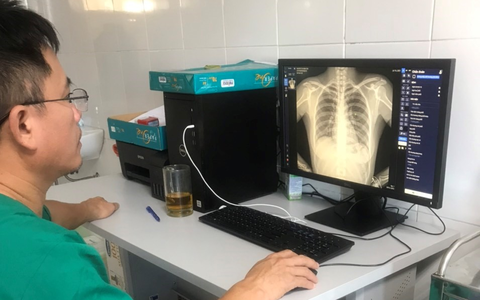

Sản phẩm DrAid™ của VinBrain vừa chính thức được Cơ quan Quản lý Thực phẩm và Dược phẩm Hoa Kỳ (FDA) ra công văn chấp thuận.

Nếu vượt qua những bài kiểm tra khắt khe từ FINDDX, Tổ chức y tế thế giới (WHO) sẽ chứng thực sản phẩm DrAid™ của VinBrain được phép ứng dụng trên phạm vi toàn cầu.

DrAid - phần mềm chẩn đoán hình ảnh y tế do VinBrain (Tập đoàn Vingroup) nghiên cứu, phát triển dựa trên bộ dữ liệu lớn nhất Việt Nam gồm 1,3 triệu hình ảnh X-quang với sự tham gia của gần 1.000 bác sĩ tại hơn 100 bệnh viện.